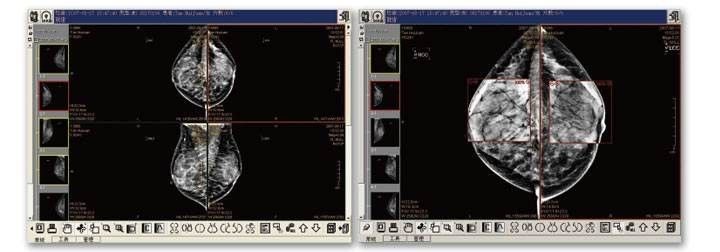

2、MIP(最大密度投影)将三维数据向某方向进行投影,取投影线经过的所有体素中最大的一个体素值,作为结果图像的像素值。适用于高密度组织结构和病灶的显示,如CTA、血管壁钙化、气管通畅情况等。它体现了密度信息,但不能测量CT值。